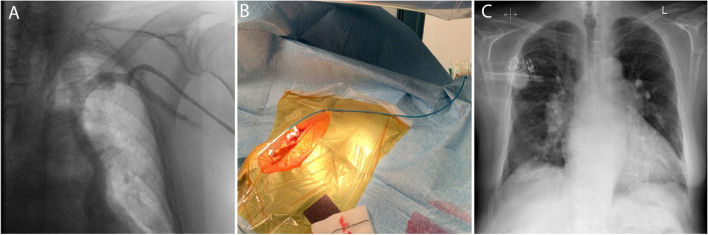

Fig. 2.

Images of chest x-ray fluoroscopy and manual modification of the C315-HIS delivery sheath. A A venography of left subclavian vein showing left superior persistent vena cava. B Reshaping point and the presumed septal region was estimated by placing the sheath on the body surface under fluoroscopy. C A chest X-ray of the final lead position

Venography on the left side showed a persistent left superior vena cava (Fig. 2A). A decision was made to attempt LBBAP lead implantation from the right side. To enable SelectSecure 3830 69 cm pacing lead (Medtronic Inc., Minneapolis, MN, USA) positioning and adequate support for transseptal screwing, the delivery sheath C315-HIS (Medtronic Inc., Minneapolis, MN, USA) was manually modified with dilator in place by creating a 90-degree curve at the right subclavian vein-superior vena cava junction. The distance between the reshaping point and the presumed septal region was estimated by placing the sheath on the body surface under fluoroscopy (Fig. 2B). The sheath was then inserted through the guidewire from the right subclavian vein access to the basal part of the RV septum as previously described. Then, in right anterior oblique 200 the pacing lead was inserted into the delivery sheath to find the initial pacing site, where the V1 lead appeared to be W-shaped. The modification of the C315-HIS catheter allowed perpendicular positioning of the lead tip to the interventricular septum in left anterior oblique 300 with minimal torque. The fluoroscopic image of the final pacing lead implantation site can be viewed in Fig. 3A. Subsequently, the lead was gradually screwed transeptally until unipolar pacing at the site showed a right bundle branch block QRS morphology with a notch in the nadir of the QS complex. With the time interval from stimulus to peak of R wave in lead V6 of 80 ms, isoelectric interval on intracardiac electrogram, and the V6-V1 interpeak interval of 50 ms LBB capture was confirmed (Fig. 1C) [3]. Pacing parameters were excellent: R-wave sensing 15.4 mV, threshold 0.75 V at 0.5 ms, and unipolar pacing impedance 646 Ohm. The lead was connected to dual-chamber pacemaker device in the ventricular port, while a pin was inserted in the atrial port (Fig. 2C). Dual-chamber device was selected in case of any additional lead insertion in the future, e.g. in case of sinus rhythm restoration. The total procedural time was 50 minutes and the fluoroscopy time was 7.4 minutes. During and after the procedure the patient reported no chest pain or other adverse events and there were no ST-T changes present on native 12-lead ECG. AV node ablation with non-irrigated ablation catheter was performed the next day (Fig. 3B). The periprocedural LBBAP lead parameters remained stable. Pacemaker was set to VVIR pacing with 80 bpm rest rate (Fig. 1B).